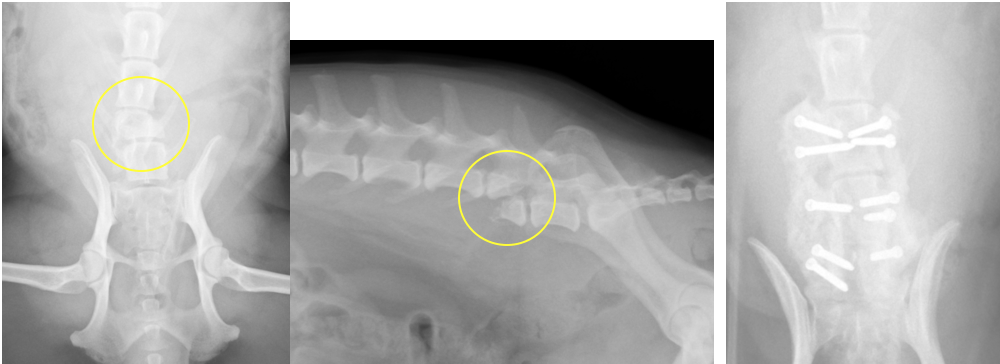

椎体骨折・椎体不安定に対する椎体固定術

交通事故などで背骨が折れてしまったり、椎間板の問題でズレが生じ不安定性がある場合、背骨の中を通る脊髄に障害をきたし、歩行異常や麻痺などの症状が出ます。また、大きな血管を損傷し、死に至る場合もあります。椎体骨折や椎体不安定の場合、椎体を何らかの方法で固定し、元の位置に安定化させる必要があります。小型犬〜中型犬で安全性が高く強固な固定は、折れている(ずれている)背骨とその前後の椎体にスクリューを打ち込み、打ち込んだスクリューを骨セメント(PMMA)という物質で固める方法です。他にもプレートやピンを使用する方法もあります。 手術自体は難易度が高いのですが、Cアームという透視装置を導入したことで以前ほどの危険性はなくなりました。

椎間板の問題で椎体にずれが生じた症例です。骨折ほど大きなズレではないため、片側からスクリューを打ち込み、それを骨セメントで固定しています。この症例は椎間板ヘルニアの手術で減圧術(ヘミラミネクトミー)も同時に行いました。術後の経過はよく、うまく歩けなかったのが、通常通り歩けるようにまでなりました。